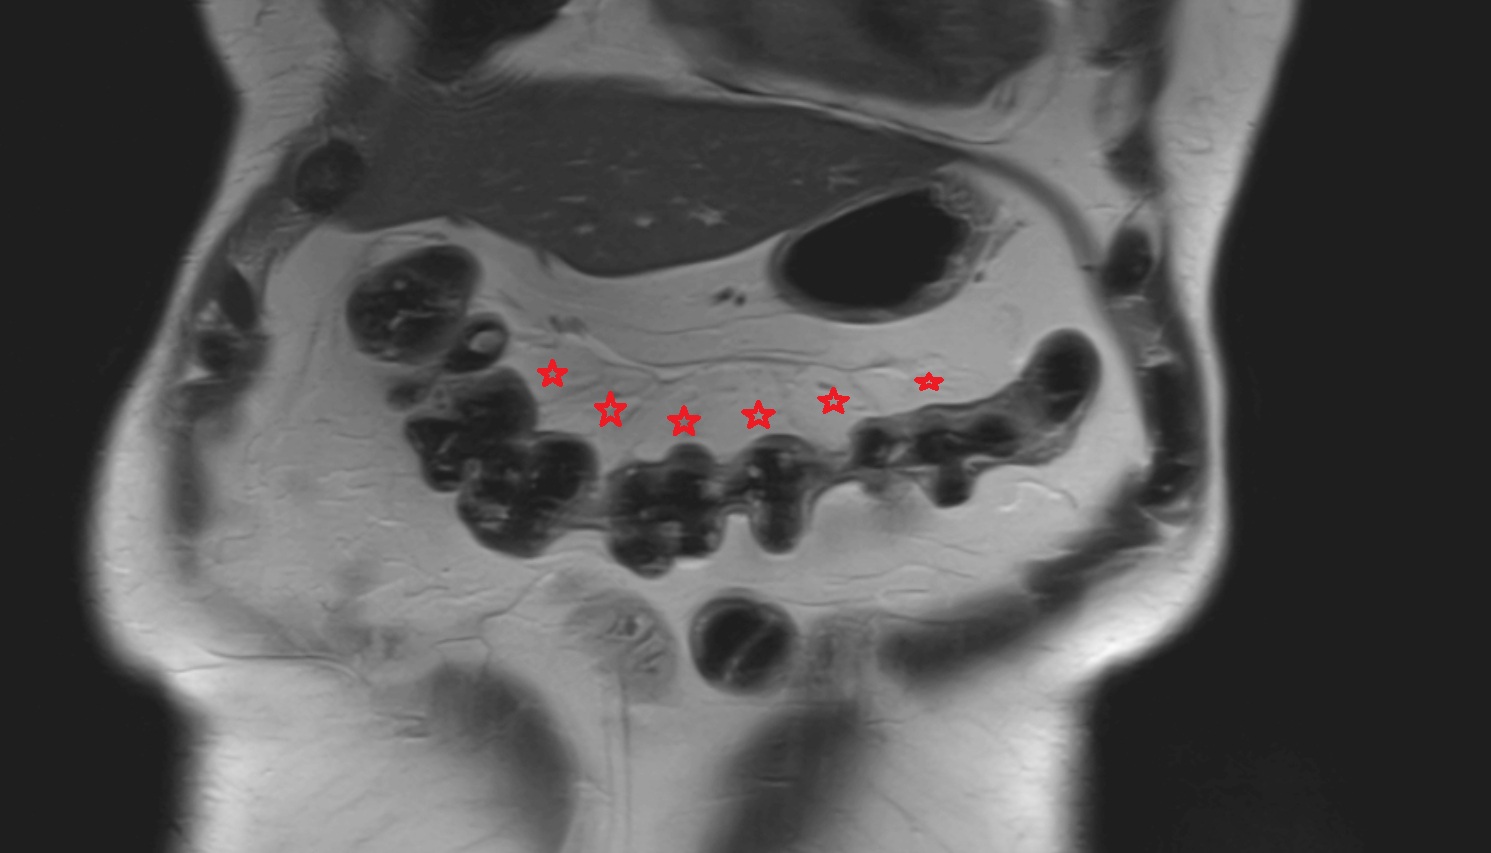

- Maternal ovaries

- Ovaries

- Right ovary

- Left ovary